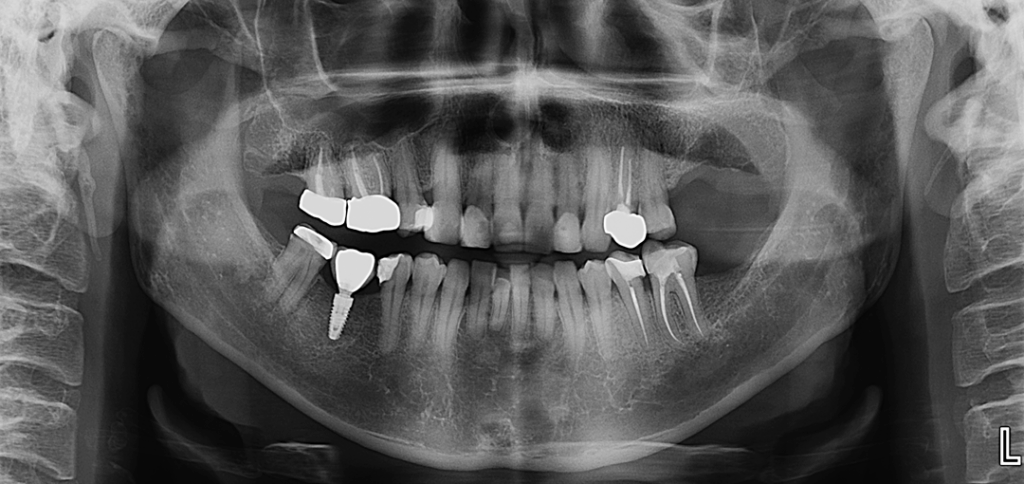

En la radiografía panorámica (Figura 1), se aprecia imagen radiolucida unilocular proyectada sobre zona anterior del maxilar superior, de limites definidos, bordes corticalizados.

Radiografia Panorámica